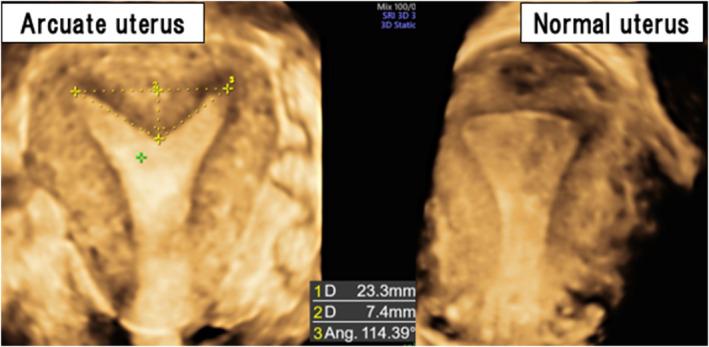

Arcuate uterus does not impact the success of infertility treatments, but there is no consensus on whether it influences perinatal outcomes. The objective of the present study was to investigate whether minor congenital uterine anomalies such as an arcuate uterus contribute to perinatal complications. This was a retrospective cohort study at a single institution. The study included 1097 deliveries after 22 weeks of gestation. Transvaginal ultrasound, with three-dimensional functionality, assessed uterine morphology based on American Society for Reproductive Medicine criteria. We compared maternal backgrounds and perinatal complications between arcuate uterus and normal uterus groups. Statistical analyses, including multivariate analysis, aimed to identify independent risk factors. A total of 69 patients (7.5%) with diagnosed arcuate uterus were included. Maternal background factors showed no significant differences between groups. In perinatal complications, an arcuate uterus was associated with a significantly higher incidence of preterm delivery (13% versus 4.7%, P = 0.01), preterm premature rupture of membranes (7.2% versus 1.6%, P = 0.01), fetal growth restriction (FGR; 16% versus 6.7%, P = 0.01), and abnormal placental cord insertion (33% versus 7.6%, P < 0.01). After multivariate analysis, arcuate uterus emerged as an independent risk factor for preterm delivery (adjusted odds ratio [aOR], 4.0 [95% confidence interval (CI), 1.6-9.9], P < 0.01), FGR (aOR, 2.6 [95% CI, 1.2-5.6], P = 0.02), and abnormal placental cord insertion (aOR, 6.0 [95% CI, 3.4-10.6], P < 0.01). Arcuate uterus stands as an independent risk factor for preterm delivery, FGR, and abnormal placental cord insertion. The findings emphasize the importance of recognizing even minor uterine morphological abnormalities in assessing and managing perinatal complications.

弓形子宫不影响不孕治疗的成功率,但对于它是否会影响围产期结局尚无共识。本研究的目的是调查诸如弓形子宫等轻微先天性子宫异常是否会导致围产期并发症。这是一项在单一机构进行的回顾性队列研究。该研究纳入了妊娠22周后分娩的1097例产妇。采用具有三维功能的经阴道超声,根据美国生殖医学学会标准评估子宫形态。我们比较了弓形子宫组和正常子宫组的产妇背景和围产期并发症。包括多变量分析在内的统计分析旨在确定独立危险因素。总共纳入了69例(7.5%)诊断为弓形子宫的患者。两组间产妇背景因素无显著差异。在围产期并发症方面,弓形子宫与早产(13%对4.7%,P = 0.01)、早产胎膜早破(7.2%对1.6%,P = 0.01)、胎儿生长受限(FGR;16%对6.7%,P = 0.01)以及胎盘脐带插入异常(33%对7.6%,P < 0.01)的发生率显著较高相关。多变量分析后,弓形子宫成为早产(调整优势比[aOR],4.0[95%置信区间(CI),1.6 - 9.9],P < 0.01)、FGR(aOR,2.6[95%CI,1.2 - 5.6],P = 0.02)和胎盘脐带插入异常(aOR,6.0[95%CI,3.4 - 10.6],P < 0.01)的独立危险因素。弓形子宫是早产、FGR和胎盘脐带插入异常的独立危险因素。这些发现强调了在评估和管理围产期并发症时识别即使是轻微子宫形态异常的重要性。